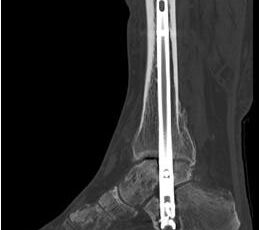

Implantation des Nagels und BV-Kontrolle (Video 5). Schließlich erfolgt die Verriegelung des Nagels über entsprechende Zielvorrichtungen. Bei einigen Nageltypen gibt es nageleigene Kompressionsmechanismen, die eine zusätzliche Drucksteigerung im Bereich der Arthrodeseflächen des ehemaligen oberen und unteren Sprunggelenkes erlauben (Video 6). Die abschließende BV-Kontrolle in beiden Ebenen sollte eine regelrechte Stellung der Arthrodese mit 90° - Stellung im Rückfuß, in der anderen Ebene mit einem Rückfußvalgus von ungefähr 5° zeigen.

• Primäre oder posttraumatische Arthrose des OSG und USG (Abbildung 1, Abbildung 2).

• Revision einer gescheiterten Fusion des OSG/ USG (Abbildung 3, Abbildung 4).

• Pseudarthrosen (Abbildung 5, Abbildung 6).